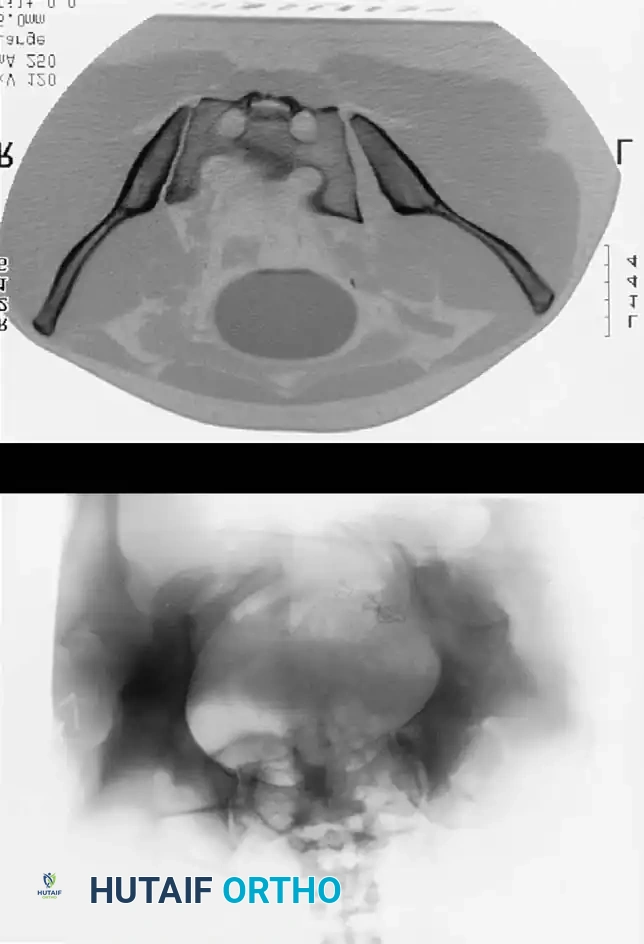

The following gallery demonstrates the progression of complex pelvic ring reconstructions, highlighting advanced imaging, intraoperative fluoroscopy, and definitive fixation constructs.

Advanced Imaging and Preoperative Planning

Image

Intraoperative Fluoroscopy and Reduction Techniques